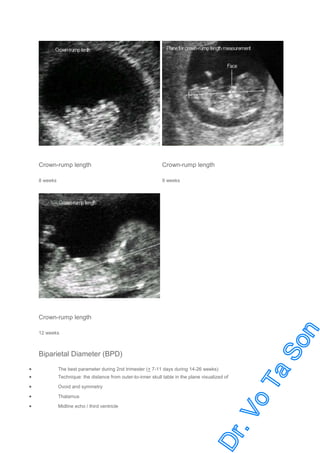

Crown-Rump Length (CRL)

The most accurate parameter for GA (+ 3-7 days)

Limitation: Appropriate only in first trimester

Technique:

Mid-sagittal scan (note fetal nose, spine, crown and rump)

Measurement from the topmost of head to rump end

Precaution: best done in neutral position, not include yolk sac or limbs

Most accurate during 6.5-10 weeks

Crown-rump length

8 weeks

9 weeks

12 weeks

Biparietal Diameter (BPD)

The best parameter during 2nd trimester (+ 7-11 days during 14-26 weeks)

Ovoid and symmetry

Thalamus

Midline echo / third ventricle

Technique: the distance from outer-to-inner skull table in the plane visualized of